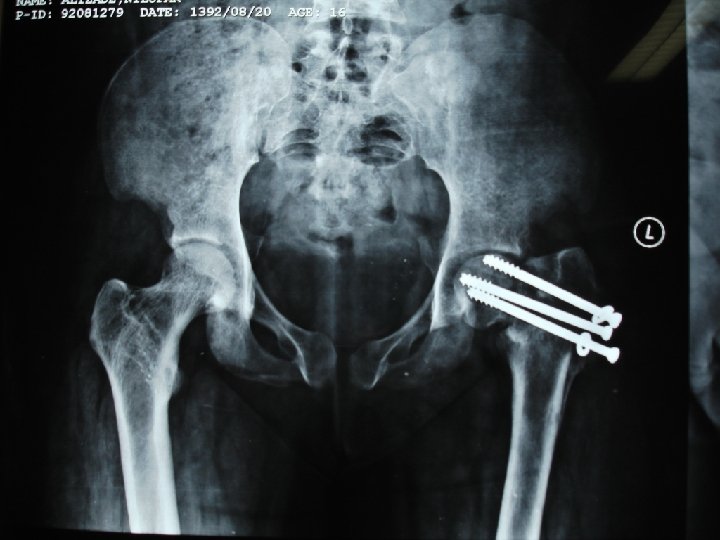

Radiological Findings Multiple bone cysts, Multiple bony fractures involving: Hip Femur Tibia ¨ Spines KUB: Bilateral renal stone disease

Proximal femural fracture

Bilateral proximal tibial fractures